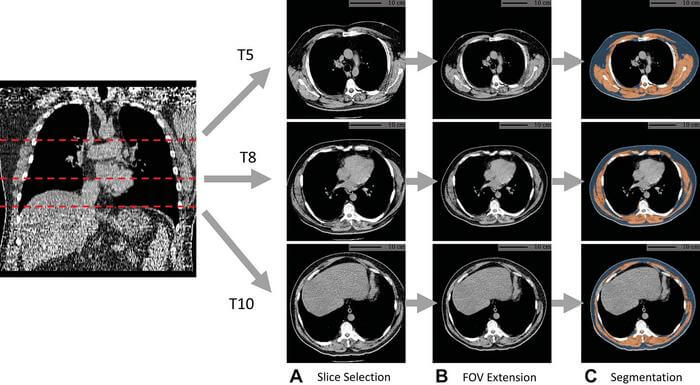

Previously, Xu and colleagues have developed, tested, and publicly released an AI algorithm that automatically derives body composition measurements from lung screening CT scans. These measures capture the percentage of fat, bone, and muscle in the body. Instances of abnormal body composition like obesity and loss of muscle mass are associated with chronic health conditions like heart disease. In fact, studies have shown that body composition is useful in identifying risk and prognosis for cardiovascular disease and chronic obstructive pulmonary disease (COPD). In lung cancer therapy, it has been shown to impact survival and overall quality of life.

During this study, the team assessed the value added by AI body composition measurements by using CT scans of over 20,000 individuals from the National Lung Screening Trial. They found that by including these measurements, predicting lung cancer, heart disease, and all-cause mortality death risk was improved.